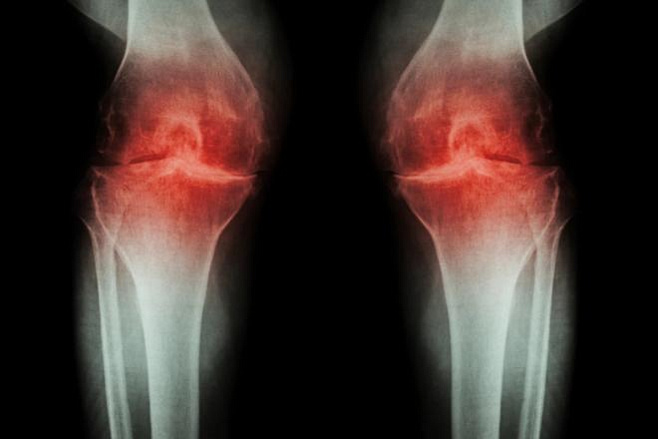

Суставной хрящ — это мягкая амортизирующая ткань, которая находится между костями. По мере изнашивания или из-за повреждения могут развиться постоянная боль и воспаление, что приводит к артриту и другим заболеваниям суставов.

В новом исследовании ученые попытались определить эффективность метода, называемого микропереломом. Процесс лечения включает в себя просверливание крошечных отверстий на поверхности сустава, что стимулирует скелетные стволовые клетки сустава создавать новую ткань. Микротрещины приводят к образованию так называемого фиброзного хряща, который больше похож на рубцовую ткань, нежели на естественный хрящ. Он покрывает кость, но не обладает упругостью и эластичностью, и сравнительно быстро разрушается.

В экспериментах на мышах ученые использовали молекулу, называемую костным морфогенетическим белком два (КМБ2), чтобы мотивировать образование новой кости после процедуры микроперелома. Но прежде, чем этот процесс полностью завершился, они остановили его в нужное время, заблокировав молекулу, называемую фактором роста эндотелия сосудов (VEGF). И это сработало.

«В итоге мы получили хрящ, который состоит из клеток того же типа, что и естественная ткань, и имеет сопоставимые механические свойства, — говорит автор исследования. — Выращенный хрящ восстановил подвижность мышей с остеоартритом и значительно уменьшил боль».